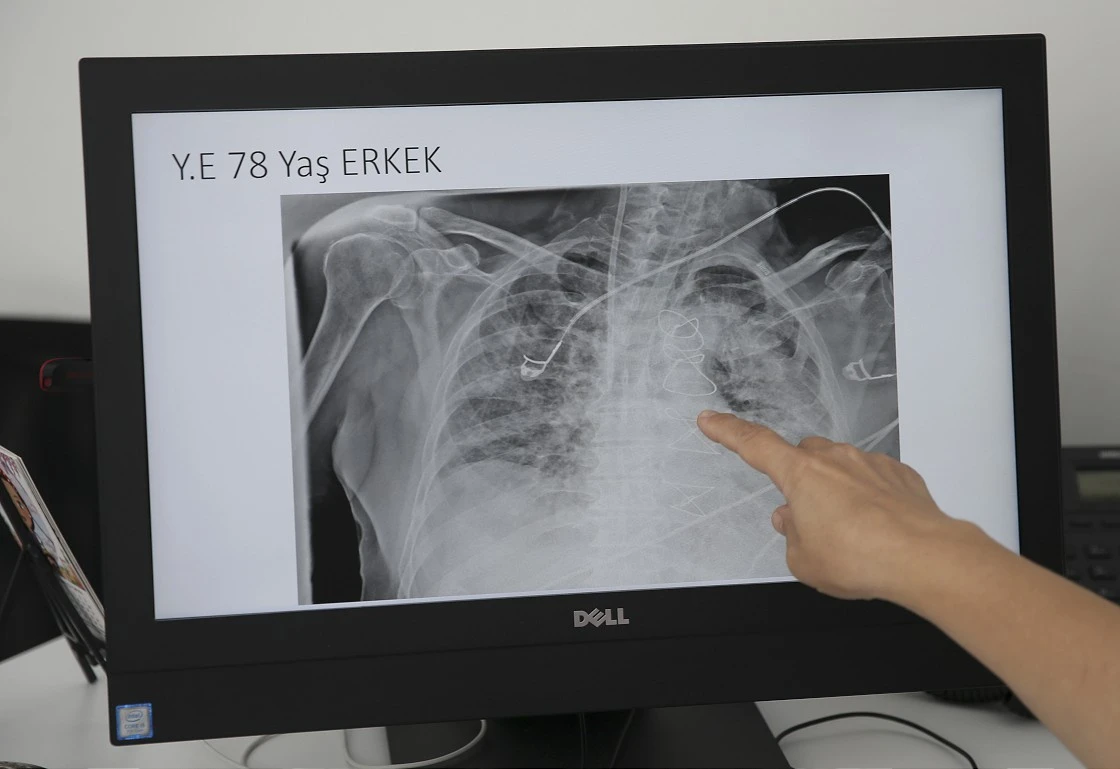

Prof. Dr. Karalezli, koronavirüs tedavisi gören hastalara ait akciğer görüntülerinden hastalığın yol açtığı tahribatı ve hastalar üzerindeki etkileri anlattı.

Tedavisine rağmen nefes darlığı şikayetleri devam eden bir hastaya uygulanan akciğer görüntülemesinde hastanın her iki akciğerinin büyük bir bölümünü enfeksiyon kapladığını tespit ettiklerini ifade eden Karalezli, "Bu hastalığın sonunun ne olduğunu bilmiyoruz. Akciğer tutulumları, bu şekilde olduğu zaman hastaları oksijen tedavisi ile gönderiyoruz. Çok yeni bir hastalık olduğu için bu seyir nasıl olacak? Geriye dönüş var mı? Takiplerle öğrenebileceğimiz bir durum." dedi.

Normal akciğer görüntüleri ile koronavirüs hastalarının akciğer görüntüleri arasında ciddi farklar bulunduğunu belirten Karalezli, şu bilgileri verdi:

"İnsanların aradaki farkları anlamaları için her iki akciğer görüntülerine de yer verdim. Görüntülerdeki beyazlıklar akciğerdeki tutulumu gösteren görüntüler ne yazık ki. Bu hastalar yoğun bakım hastaları. Filmler birbirine az çok benzeyen şekilde. Altta yatan hastalığı olanlarda ise daha kötü seyrediyor."